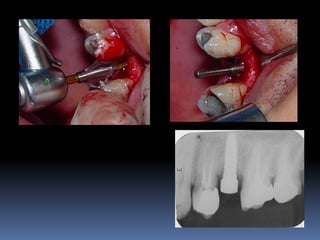

Guia cirúrgico

•Permite o posicionamento ideal da fresagem

através de orifício em guias transparentes

•Utilização de tubos, cones ou somente orifícios

realizados por fresas

•Liberdade controlada da fresa

Hassem e Valsani

Duplicação de prótese total

Confecção de Guia Cirúrgico

Enceramento

Posicionamento ideal

Tubos com lâmina de vácuo-press

Aplicação prática